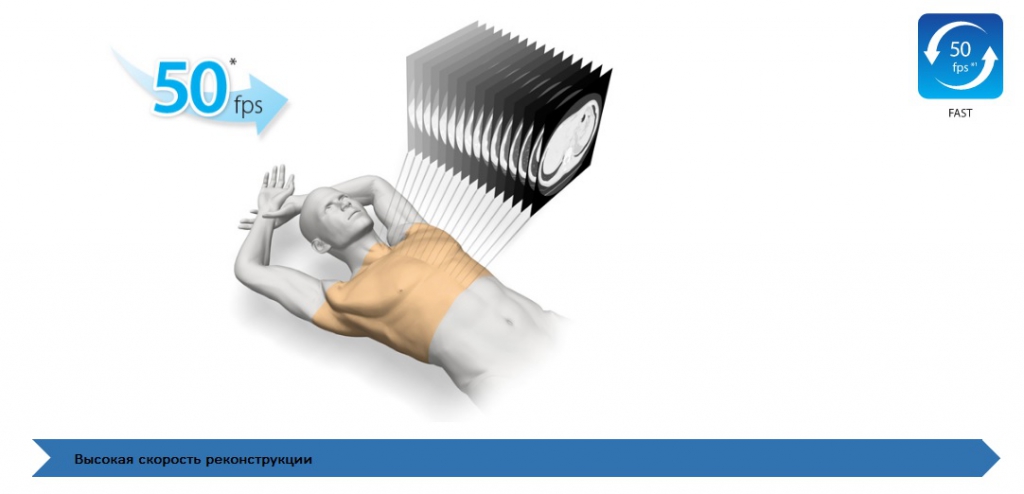

Быстрая реконструкция

При скорости реконструкции до 50 изображений в секунду при полном разрешении, обеспечивается высокая пропускная способность пациента.